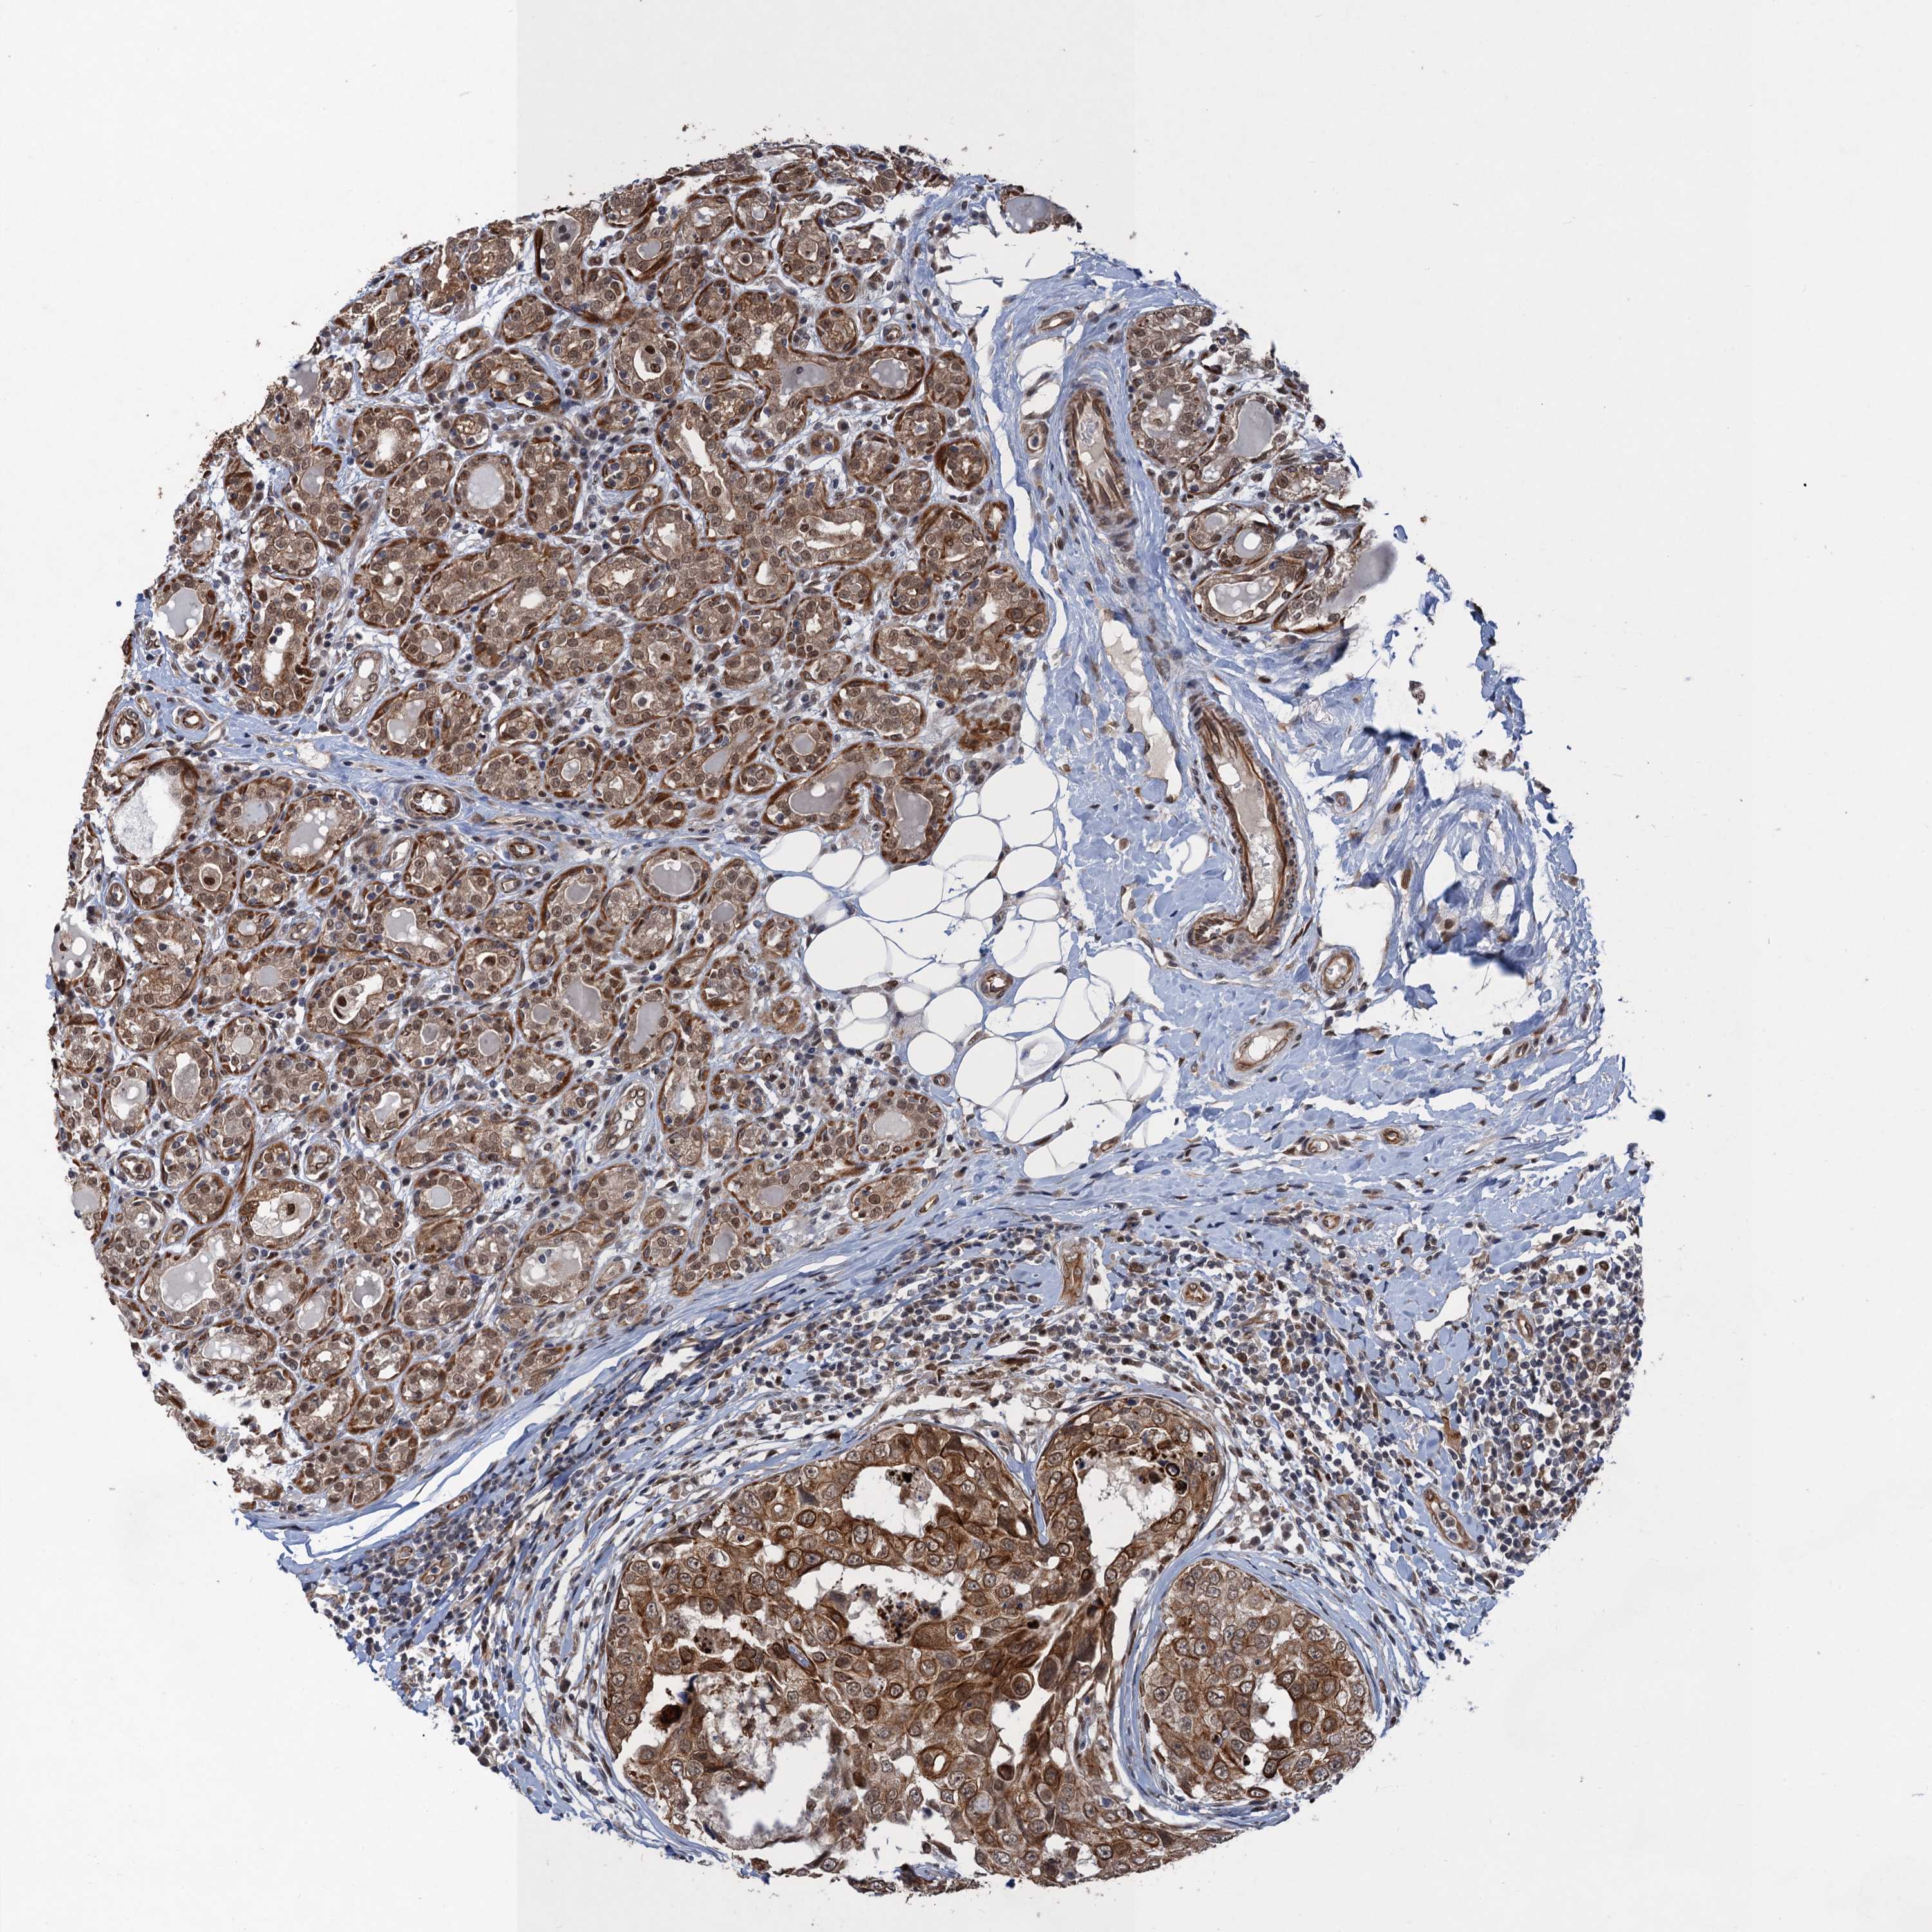

CANCER BREAST CANCER Show tissue menu

BRCA TCGA BRCA VALIDATION PROTEIN EXPRESSION